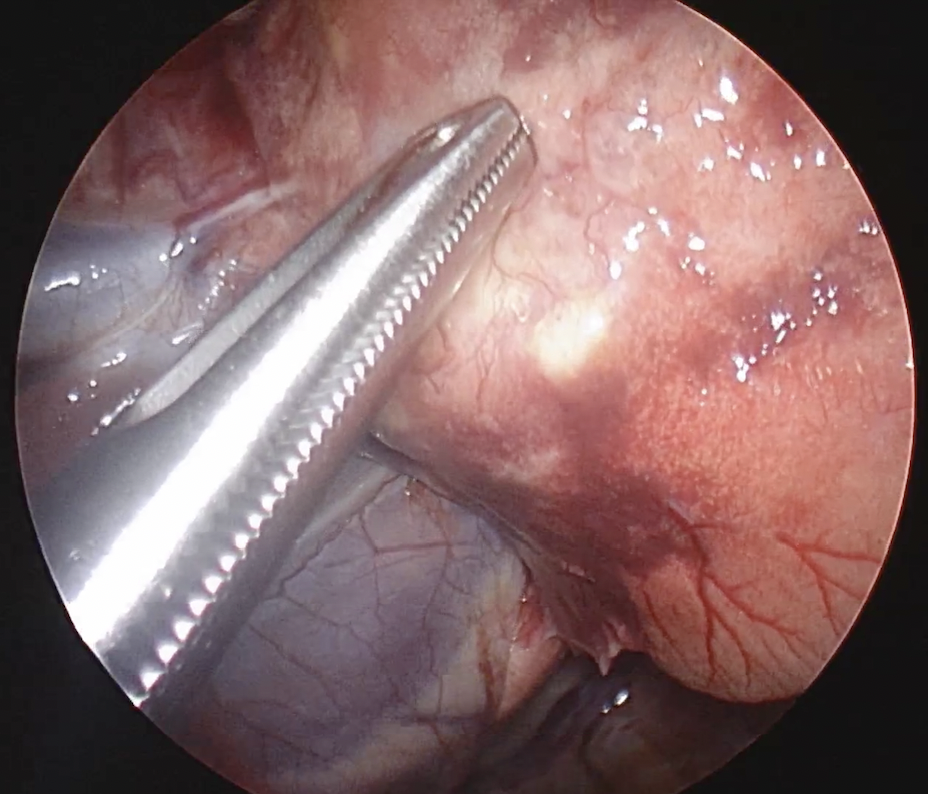

胸の中に鉗子を入れているところ